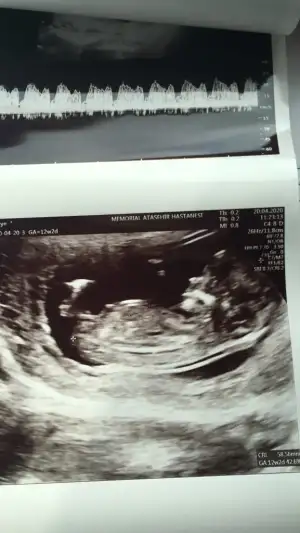

akadaşlar merhaba, ultrason görüntülerini paylaşsam bakabilir misiz.? meraktan çatlıyor insan 😍

Ultrason görüntülerimiz😍

• C5D6BCE4-511E-4694-BA9C-FAD0D1AB8020.webp

C5D6BCE4-511E-4694-BA9C-FAD0D1AB8020.webp

31,7 KB · Görüntüleme: 56

yaa 😍 bende kız diye gördüm ama emin olamadım. bu nub teorisi inşallah doğrudur 😂 allah gönlümüze göre versin 😊 senin bebişin cinsiyeti kesinleşti mi peki

Yok canım 14 de gittim giremedi kemik.yapısı kız dedi ama kordon un arkasında bir şey de var sanki dedi ogrenemdim inşaallah bu teori doğrudur da kız olur 😂😂